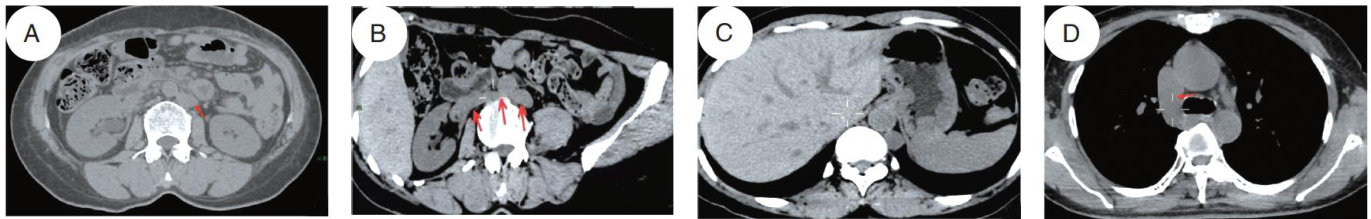

摘要目的:分析机器人辅助置钉联合矫形术后脊柱侧弯患者肺部并发症影响因素并探讨相应的管理策略。方法:选取2022年1月—2024年3月于清华大学附属北京清华长庚医院接受机器人辅助置钉联合矫形术治疗的103例脊柱侧弯患者为研究对象。根据患者术后2个月内是否出现肺部相关并发症分为发生组( n=17 )和未发生组( n=86 )。比较两组基础人口学资料、病情资料以及手术资料,Logistic单因素及多因素分析脊柱侧弯患者经机器人辅助置钉联合矫形术治疗后肺部并发症影响因素,建立受试者工作特征(ROC)曲线评估影响因素预测效能,根据影响因素探讨相应的管理策略。结果:与未发生组相比,发生组营养不良、卧床时间 ?1 周占比更高,白细胞计数水平更高,手术时间更长( P<0.05 )。单因素Logistic回归分析显示营养状况、卧床时间、白细胞计数、手术时间为患者肺部相关并发症发生的影响因素( P<0.05 )。多因素Logistic回归分析显示营养不良、白细胞计数高及手术时间延长会增加患者肺部相关并发症发生风险( P<0.05 )。营养状况、白细胞计数、手术时间单独及联合预测曲线AUC分别为 0.708,0.857,0.748,0.941 。结论:营养不良、白细胞计数高及手术时间延长会增加患者肺部相关并发症发生风险,临床需优化术前评估及术后管理方案以预防术后肺部并发症。